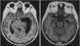

Localized temporal horn hydrocephalus